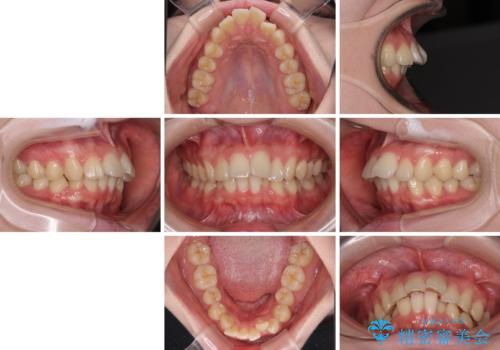

- 下顎の前歯が上顎の歯肉に咬みこむくらいに突出した上顎前歯を気にして来院された患者様です。

口元の突出感はないものの、上顎前歯が前方に傾斜して突出しており、前後に大きなズレがあり非常に深い咬み合わせとなっていました。

前突間を改善するため、上顎左右の第一小臼歯を抜歯してワイヤー装置にて矯正治療を行うこととしました。

深い咬み合わせは上顎前歯を引っ込ませる大きな障害となるため、咬み合わせの改善が非常に重要となります。やや期間はかかりましたが、当初狙った通りの仕上がりで治療を終えることができました。